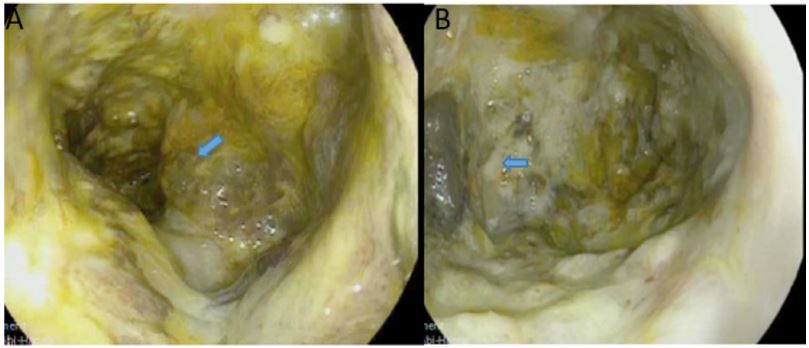

A 70-year old female was referred to the emergency department of a tertiary hospital by her general practitioner with a sixmonth history of lethargy, six-kilogram weight loss and vague right sided abdominal pain. She denied vomiting, altered bowel habit or rectal bleeding. Her relevant surgical history included cholecystectomy and thyroidectomy. There was no family history of colorectal cancer. Pertinent examination findings included a soft, non-distended abdomen with a large non-mobile palpable mass in the right upper quadrant. Her blood profile included leukocytosis (12.9 x109 /L), anaemia (Hb 79 g/L), normal bilirubin and mildly deranged liver function tests. Furthermore, she had a markedly raised CA 19.9 (5506 kU/L) and CEA (462.1 microg/L). She was admitted for a blood transfusion and further investigations. A triple phase computed tomography scan of the chest, abdomen and pelvis revealed an 11x10x10.5 cm hepatic flexure mass with invasion into the right hepatic lobe (Figure 1). Surprisingly, there was no evidence of colonic obstruction, nor distant metastatic disease. A colonoscopy demonstrated a large circumferential, fungating and partially obstructing mass extending into the ascending colon (Figure 2). Biopsy confirmed a poorly differentiated invasive adenocarcinoma (Figure 3). Following discussion at a multi-disciplinary surgical oncology meeting, she proceeded to an ileo-colonic bypass with planned adjuvant chemotherapy. Intra-operatively, the mass was invading the liver, with small amounts of ascites and no peritoneal metastasis. Proximal small and large bowel were of normal caliber. An ileo-colic side-to-side anastomosis was performed using the distal ileum and mid transverse colon. The patient made an uneventful recovery and was discharged day four post operatively with medical oncology follow up.

Figure 2: (A) Colonoscopic view of the hepatic flexure demonstrating a circumferential, fungating and partially obstructing lesion. (Blue arrow). (B) Extension into ascending colon (Blue arrow).